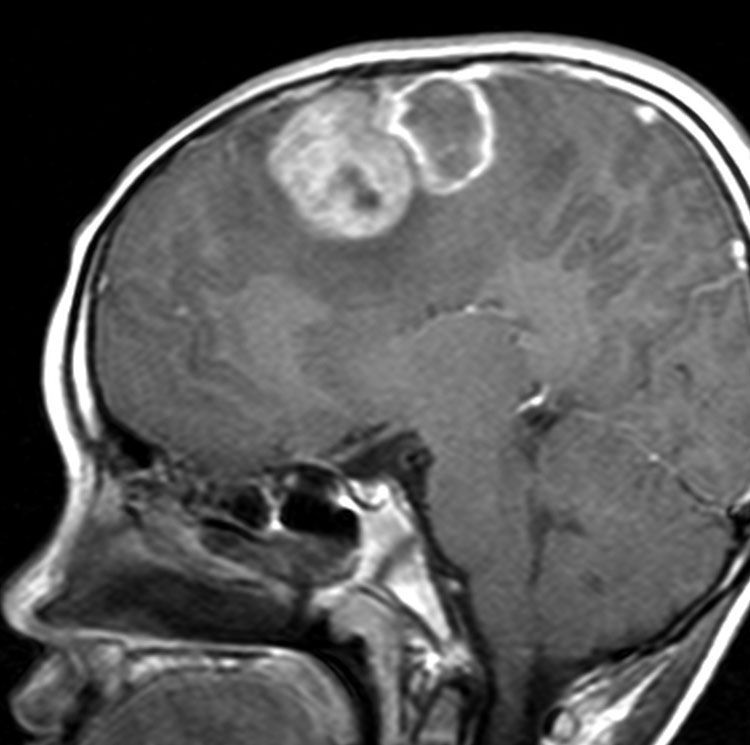

典型的な画像(膠芽腫に近い病理像の例)

特に悪性度の高かったPNETのMRI画像です。病理は膠芽腫に近い組織像でした。この子は4歳でした。小さい子供にできますが発見されたときには巨大な腫瘍になってしまっていることが多いです。この腫瘍の初回手術の時にはあふれるように出血しました。治療は,手術でなるべく全部取らないとなりません。でもこんなに大きいのを手術でいっぺんに取ると命が危ないし,摘出できても障害が大きくなりすぎますから,化学療法や放射線治療で小さくしておいてから,開頭手術で全部摘出するという方法もあります。この子供はそうしました。もし3歳以下だと放射線が使いにくいので化学療法だけになりますが,いずれにしてもPNETの治療は難しいです。

脳脊髄照射と化学療法で抑え込んで,右の写真は治療後10年経ったときのものです。大きくなってからは,高次脳機能障害と難治性てんかんで学校へ通うのが難しくなりました。